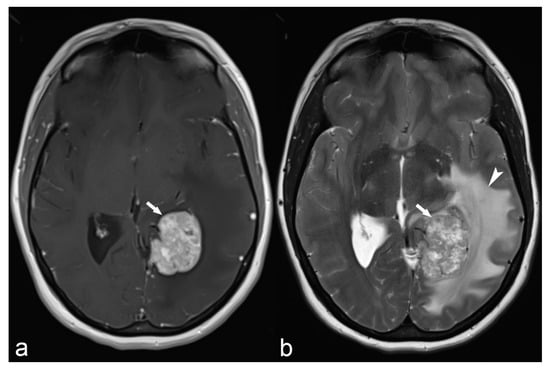

Figure 4.

36-year-old woman. The right hippocampus is smaller than the left (arrows) as seen on coronal T2WI (a), FLAIR (b) and MP2RAGE (c) and shows hyperintensity on T2WI and FLAIR. There is also flattening and loss of the normal undulations of the right hippocampus, suggestive of hippocampal sclerosis.